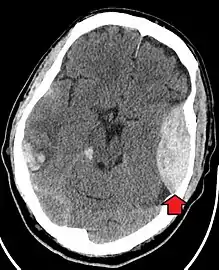

| Epidural hematoma as seen on a CT scan with overlying skull fracture. Note the biconvex shaped collection of blood. There is also bruising with bleeding on the opposite side of the brain. | |

Epidural hematomas usually appear convex in shape because their expansion stops at the skull's sutures, where the dura mater is tightly attached to the skull. Thus, they expand inward toward the brain rather than along the inside of the skull, as occurs in subdural hematomas. Most people also have a skull fracture.[3]